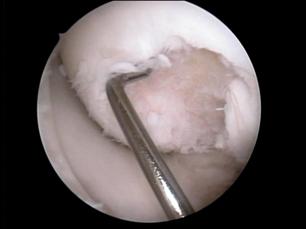

2.2.2.1. Transplantul Osteocondral Autolog

Transplantul Osteocondral Autolog este o procedura prin care se preleveazaunul sau mai multi cilindri osteocondrali dintr-o zona donoare si se implanteaza in zona defectului cartilaginos. Tehnic, se recolteaza mai multi cilindri osteocondrali dintr-o zona neportanta a genunchiului - un numar variabil si de dimensiuni variabile in asa fel incit sa se acopere suprafata defectului cit mai bine - cu un instrumentar special. In urmatorul timp operator se prelucreaza zona primitoare (a defectului condral) pina in cartilaj perijacent sanatos si de asemenea se prelucreaza suprafata osului subcondral si se practica niste gauri in osul subjacent in care se vor introduce cilindri osteocondrali recoltati anterior (fig. 4.4) [42,] Avantajele tehnicii constau in posibilitatea efectuarii intr-un singur timp operator, posibilitatea efectuarii chiar daca exista leziuni ale osului subcondral (osteocondrita, leziuni degenerative), costul redus, timp mai redus de recuperare comparativ cu implantul de condrocite autologe. Dezavantajele metodei constau in principal in efecte adverse legate de zona donoare si de limitarea suprafetei care poate fi acoperita datorita limitarii zonei de unde se pot recolta cilindri.

Indicatia actuala principala a acestei tehnici este pentru defectele condrale de la nivelul condililor femurali cu suprafata de 2-4 cm2, la pacientii activi, dar si la pacienti virstnici activi in functie de starea cartilajului in restul articulatiei.

Fig.4.4 Transplant osteocondral efectuat artroscopic: defect OC stIV B ICRS (OCD III); efectuarea tunelului prmitor; aspectul celor doua tuneluri cu sept osos intre ele; zona donoare pe versantul lateral al trohleei femurale; introducerea primului cilindru ostocondral, aspect final cu efectuarea si de microfracturi pe o zona neportanta (marginea interna a condilului) |